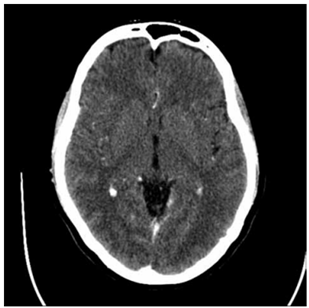

Um homem de 72 anos, hipertenso e portador de fibrilação atrial (FA) não valvar, apresenta início súbito de hemiparesia direita, afasia e desvio do olhar para a esquerda. Ele é admitido no pronto-socorro 2 horas após o início dos sintomas. A avaliação inicial revela um NIHSS de 15. A tomografia computadorizada de crânio com contraste encontra-se a seguir.

(https://radiopaedia.org/. Disponível em: https://prod-images-static.radiopaedia.org/images/4169564/65a780977632d0e771466c905c2195_gallery.jpg)

Após excluir contraindicações, o paciente é submetido a trombólise intravenosa com alteplase. Após 24 horas, uma nova tomografia não evidencia transformação hemorrágica, mas o paciente permanece com NIHSS de 12. Considerando as características do caso e o risco de transformação hemorrágica, assinale a alternativa que apresenta a melhor estratégia antitrombótica para prevenir eventos recorrentes.